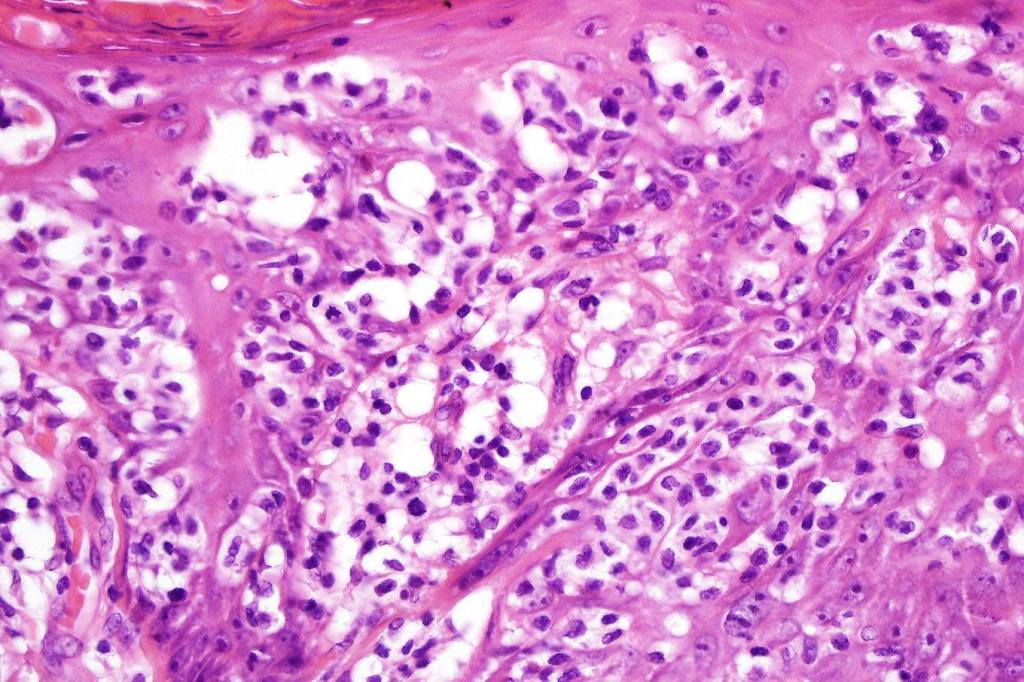

•Very marked epidermotropic infiltrate of atypical lymphocytes including Sézary cells

•Perinuclear halo often present

•Pautrier-like microabscesses

•Variable mitotic activity